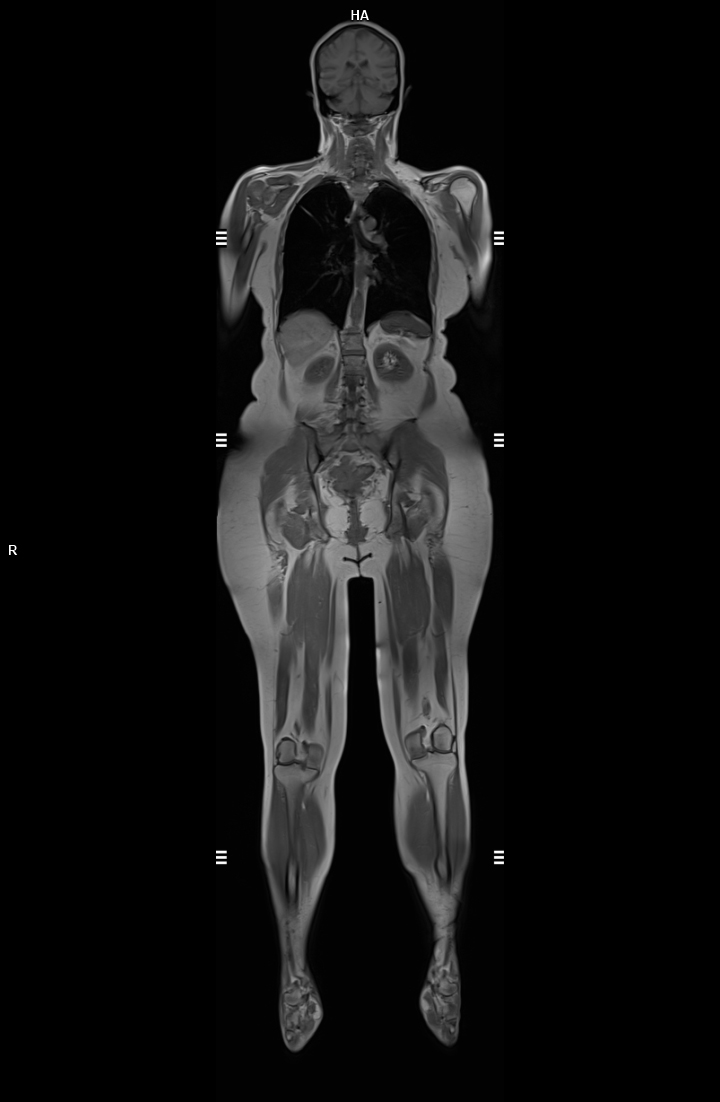

Detaylı Görüntüleme: 3 Tesla manyetik alan, daha yüksek çözünürlükte ve detaylı görüntüler sağlar. Küçük anatomik yapılar ve patolojiler daha net bir şekilde görüntülenebilir.

Zaman Tasarrufu: Daha güçlü manyetik alan, görüntüleme süresini kısaltır. Bu, özellikle hareket edemeyen veya hassas durumu olan hastalar için avantaj sağlar.

7. Geniş Uygulama Alanı

Kompleks vakaların (örneğin beyin tümörleri, kalp anomalileri) değerlendirilmesinde tercih edilir.